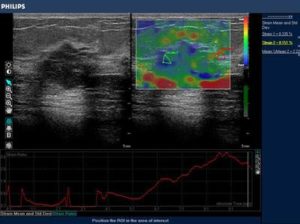

39yr old lady with history of lump in the left breast UIQ, No previous imaging done. No positive family history for CA Breast/Ovary. Pre-Menopausal Status.

Mammography- Fairly well circumscribed predominantly sold lesion in the left breast UIQ with partially obscured margins. No spiculations. No associated microcalcifications noted. Sonography: Well defined hypoechoiec lesion with smooth margins.

Low-grade Mucinous Carcinoma ER?PR- +ve HER-2 NEU -VE